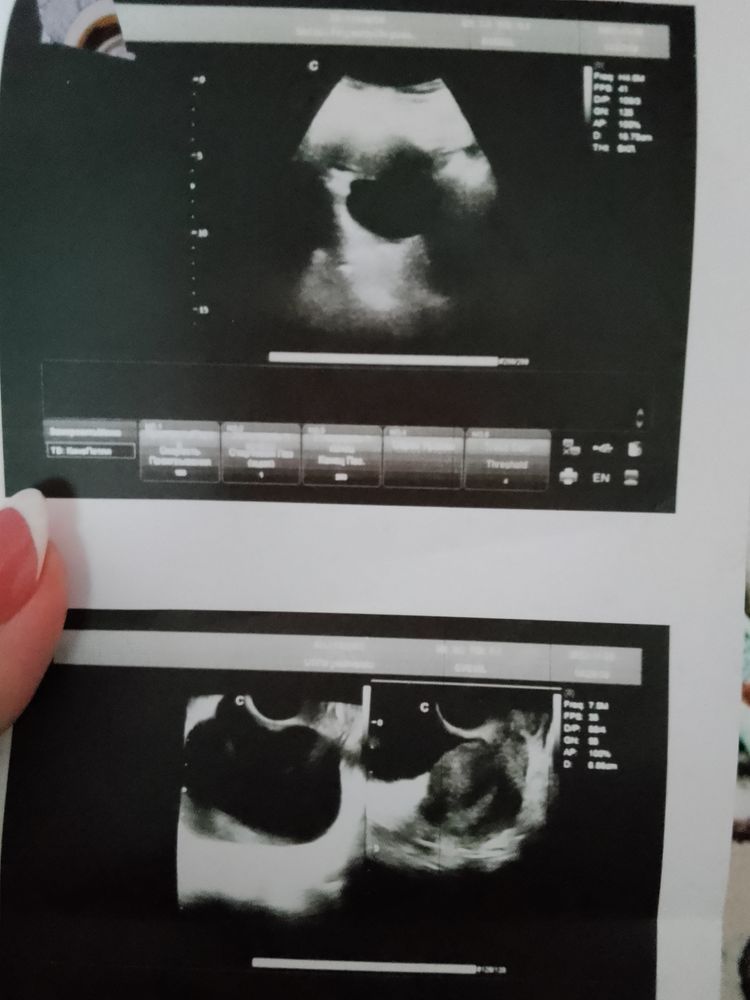

На какую кисту похоже?

Фолликулометрия

Или аппарат не очень?